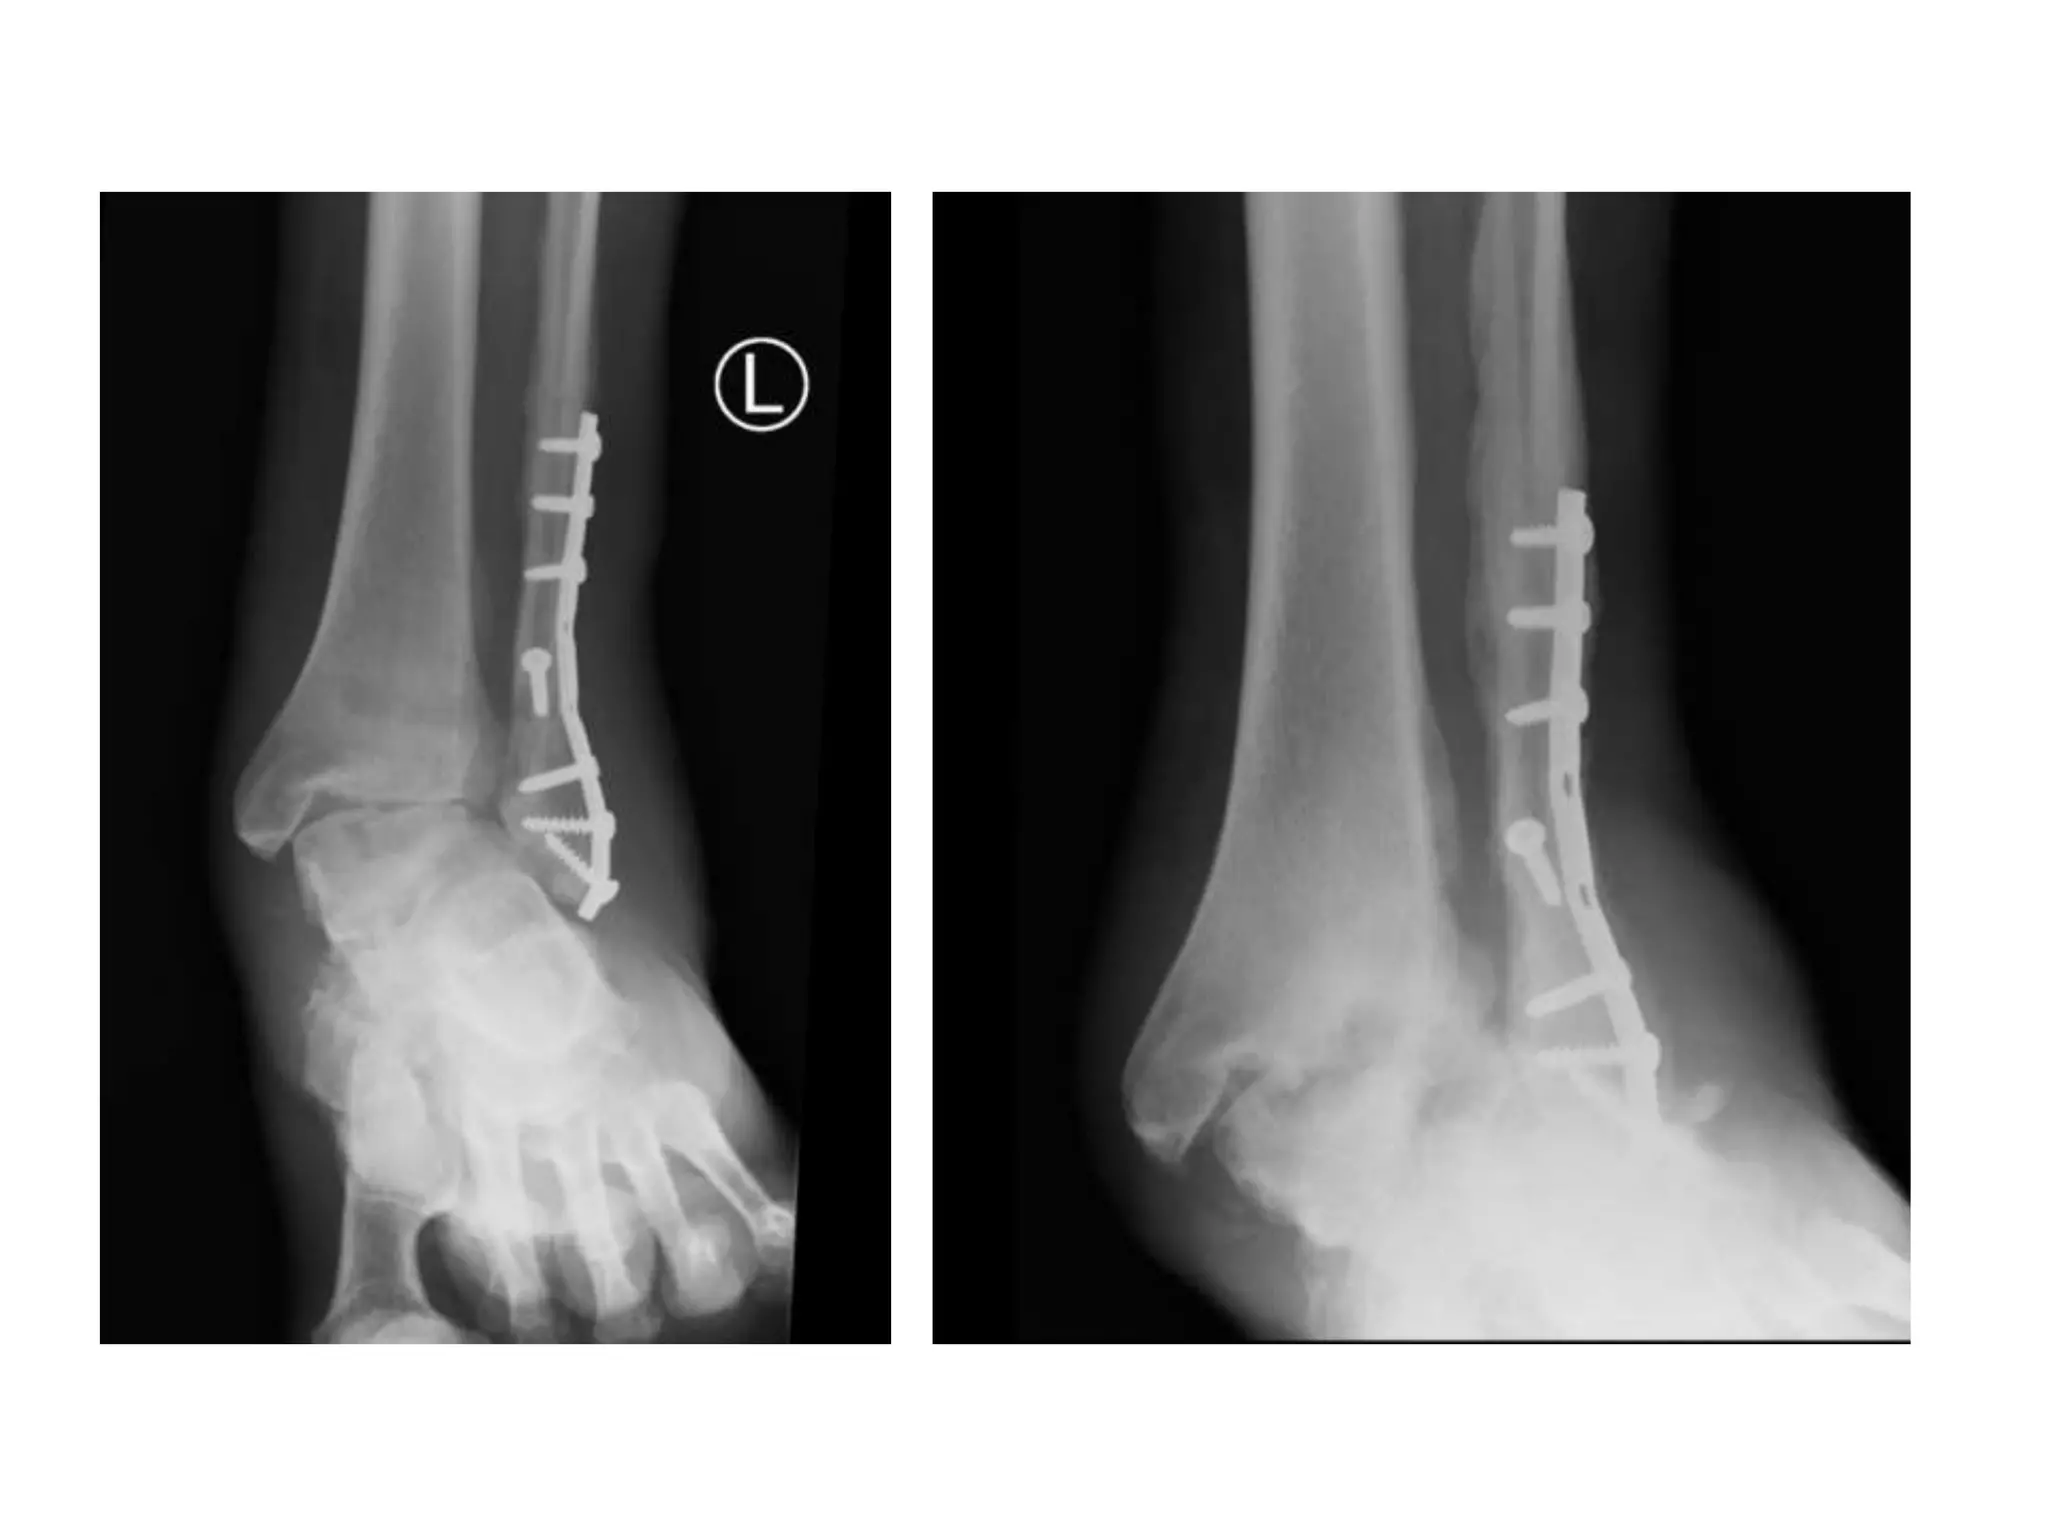

Treatment